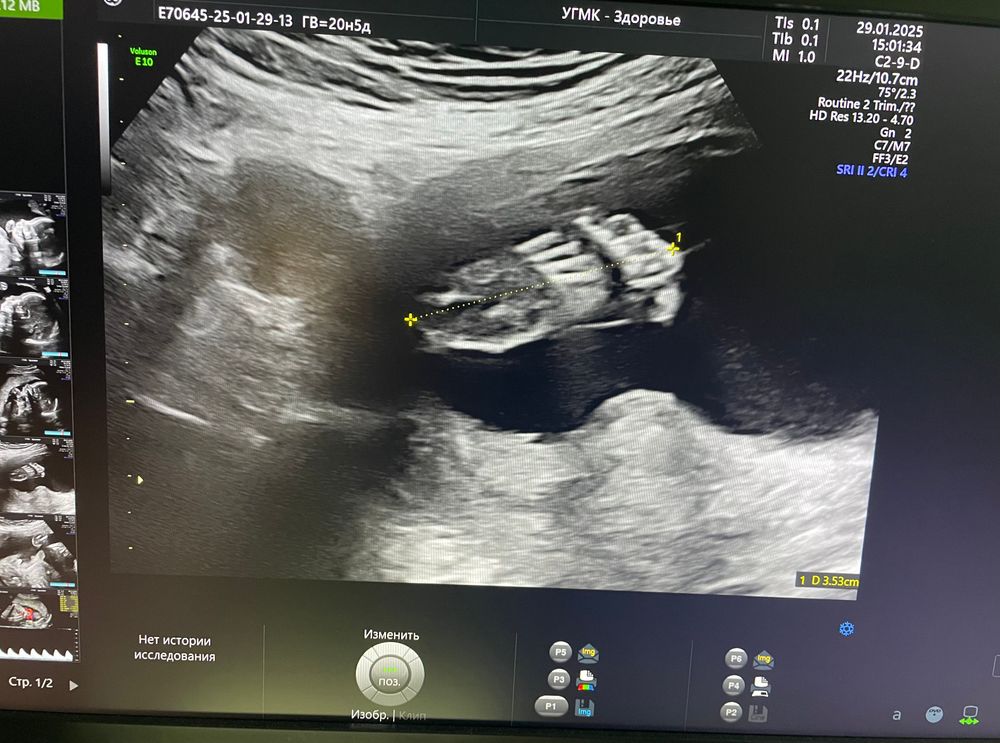

Результаты УЗИ📝пишу больше для себя)

Срок 20,4 недели

Параметры 2-го скрининга:

Бипариетальный размер - 49мм

Окружность живота - 148мм

Окружность головы - 182мм

Длина бедренной кости - 35мм

Дина плечевой кости - 33мм

Лобно-затылочный размен - 66мм

Длина носовых костей 5,9мм

Вес ~ 358гр

Толщина плаценты - 20мм

Длина шейки - 38мм

Артерия пуповины - 1,33мм

Маточная артерия (ПИ) правая - 0,61, левая - 0,82

Размещение плаценты по передней стенке матки, на 6мм выше внутреннего зева( поднялась немного, чему я очень рада, еще три недели назад перекрывала на 7мм внутренний зев).